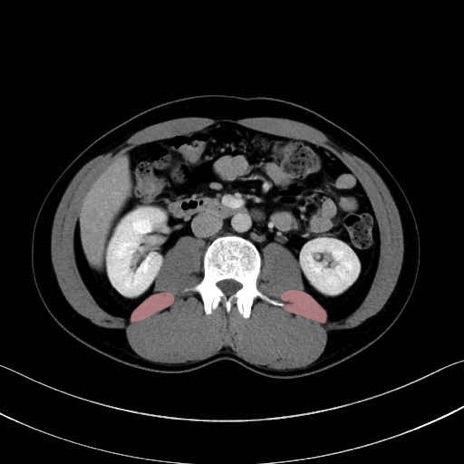

腰方形筋 (Quadratus lumborum)